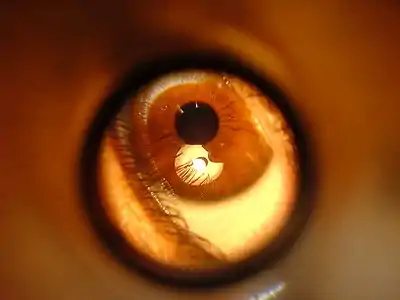

- Anatomy of the Eye

- Eye Examination